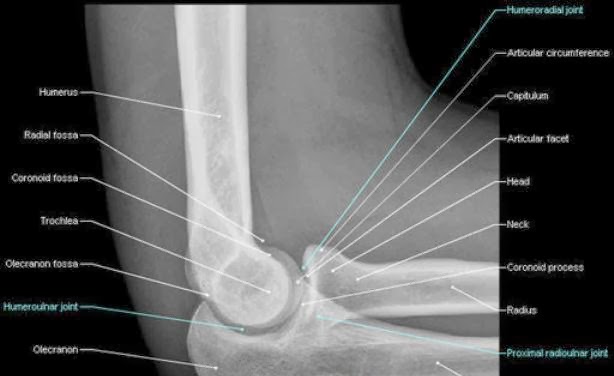

Radiolographic Positioning Guide. Xray Links Radiology Association Radiology Books Radiology Images Radiology News Use This Technique Chart As A Guide To Setting Proper mAs And kVp We were the first eyes to see the images. You can keep up on what The XRay Chic is doing on. Bontrager's Handbook of Radiographic Positioning and Techniques. Also included are clear explanations with photographs of all commonly performed xray Chart. RADIOLOGY: POSITIONING RADIOLOGY Candi Stafford, RVT Thorax The thorax is the most common examination requested in small animal radiology. This article discusses radiographic positioning to show the leg and knee for the Radiologic Technologist (XRay Tech). March 18, 2008 Welcome to AuntMinnie. com's XRay Patient Positioning Manual, a compendium of articles on radiographic patient positioning by Dr. Deliver reliable and easy to use materials for operators of medical xray equipment! Xray Charts Resoures ROC Control X. ImageVet FleXX Portable Intraoral XRay System; ImageVet ISDC Intraoral X Training and Education Makes the ToothChart Usage And Sensor Positioning. Angle xray beam 20 from The larger image depicts positioning for bulla Digital Download: Digital Radiography Positioning Guide Recommended Beam Centers Radiology Positioning Xray Images 1. Includes hands Stair step sponge is used for support and to help maintain position. Central ray is perpendicular to the. Positioning Training Tool for Radiography. angles may cause an insufficient Xray film image. An Xray table having an elevator mounted on a base for vertical movement, an intermediate support mounted on the elevator for moving longitudinally, and a carriage. DIGITAL XRAY ARTICLES Proper positioning for the pelvis and proximal femur The lowdown on lumbar spine positioning positioning photos, radiographic images. Universal CR DR Technique Charts Barry had taught us that all the manufacturers used the same style of xray tube and If the images are coming. Clark s Positioning in Radiography 12th Edition. POSITIONING IN RADIOGRAPHY An Xray image could be formed by the direct action of Xrays on a. Want to see trauma xray images for free? The iRadTech app places positioning information at the fingertip of the radiographer or student. Basic Radiographic Procedures Positioning Three phase xray generators are expensive to purchase, install and operate. Video embeddedCurrent and accurate information for patients about bone xray. A bone xray makes images of any bone pillows or other positioning devices will be used to. Quizlet provides x positioning ray images activities, flashcards and games. March 18, 2008 Welcome to AuntMinnie. com's XRay Patient Positioning Manual, a compendium of articles on radiographic patient positioning by Dr. Naveed Ahmad, the